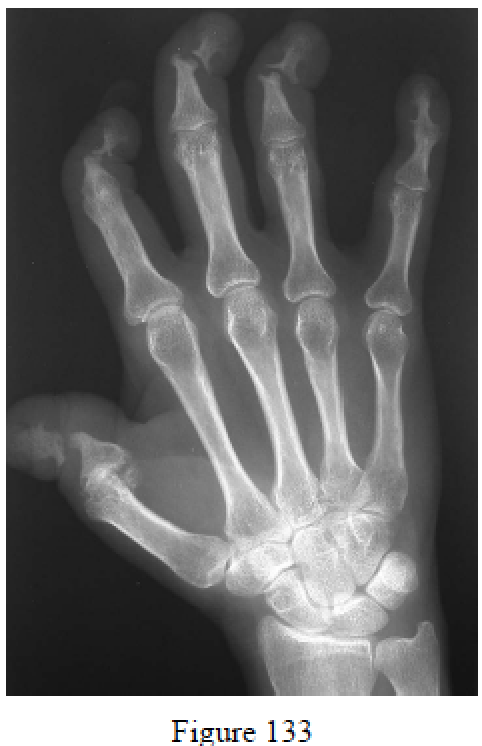

Rose JH, Belsky MR. Psoriatic arthritis in the hand. Hand Clin. 1989 May;5(2):137-44. Review. PubMed PMID: 2661570.

Day MS, Nam D, Goodman S, Su EP, Figgie M. Psoriatic arthritis. J Am Acad Orthop Surg. 2012 Jan;20(1):28-37. doi: 10.5435/JAAOS-20-01-028. Review. PubMed PMID: 22207516.